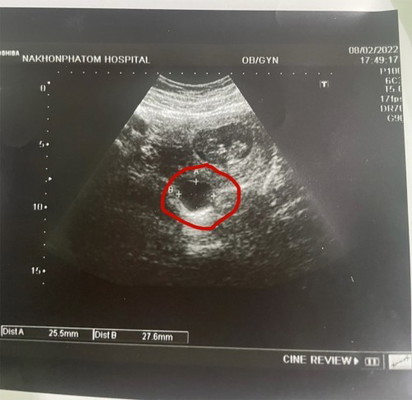

ก่อนอื่นต้องสวัสดีทุกคนในนี้ก่อนนะคะ เมื่อวานวันที่8 มีนัดไปเอกซเรย์ดูเจ้าตัวน้อย น้องก็เจริญเติบโตปกติ 10w แต่!!!มีเรื่องเซอร์ไพรส์เพิ่มอีกคือ มีถุงซีสในมดลูกใกล้กับเบบี๋ของเรา ขนาดประมาณ 1 นิ้ว เล็กกว่าตัวน้องครึ่งเซน อีก 6 อาทิตย์หมอนัดให้ไปดูขนาดเจ้าซีสน้อย ถ้าน้อนโตก็ต้องผ่า ผ่าก็มีความเสี่ยงที่จะแท้ง แต่ถ้าไม่โตก็ปล่อยไปก่อนได้ ในชีวิตนี่เจอแต่เรื่องเซอร์ไพรส์ไม่หยุดหย่อนจิงๆค่ะ ตอนแรกเครียดมากๆ ตอนนี้ทำใจคิดแค่อะไรจะเกิดก็ต้องเกิดแค่ขอให้ลูกปลอดภัยก็พอ #ท้องแรกของฉัน